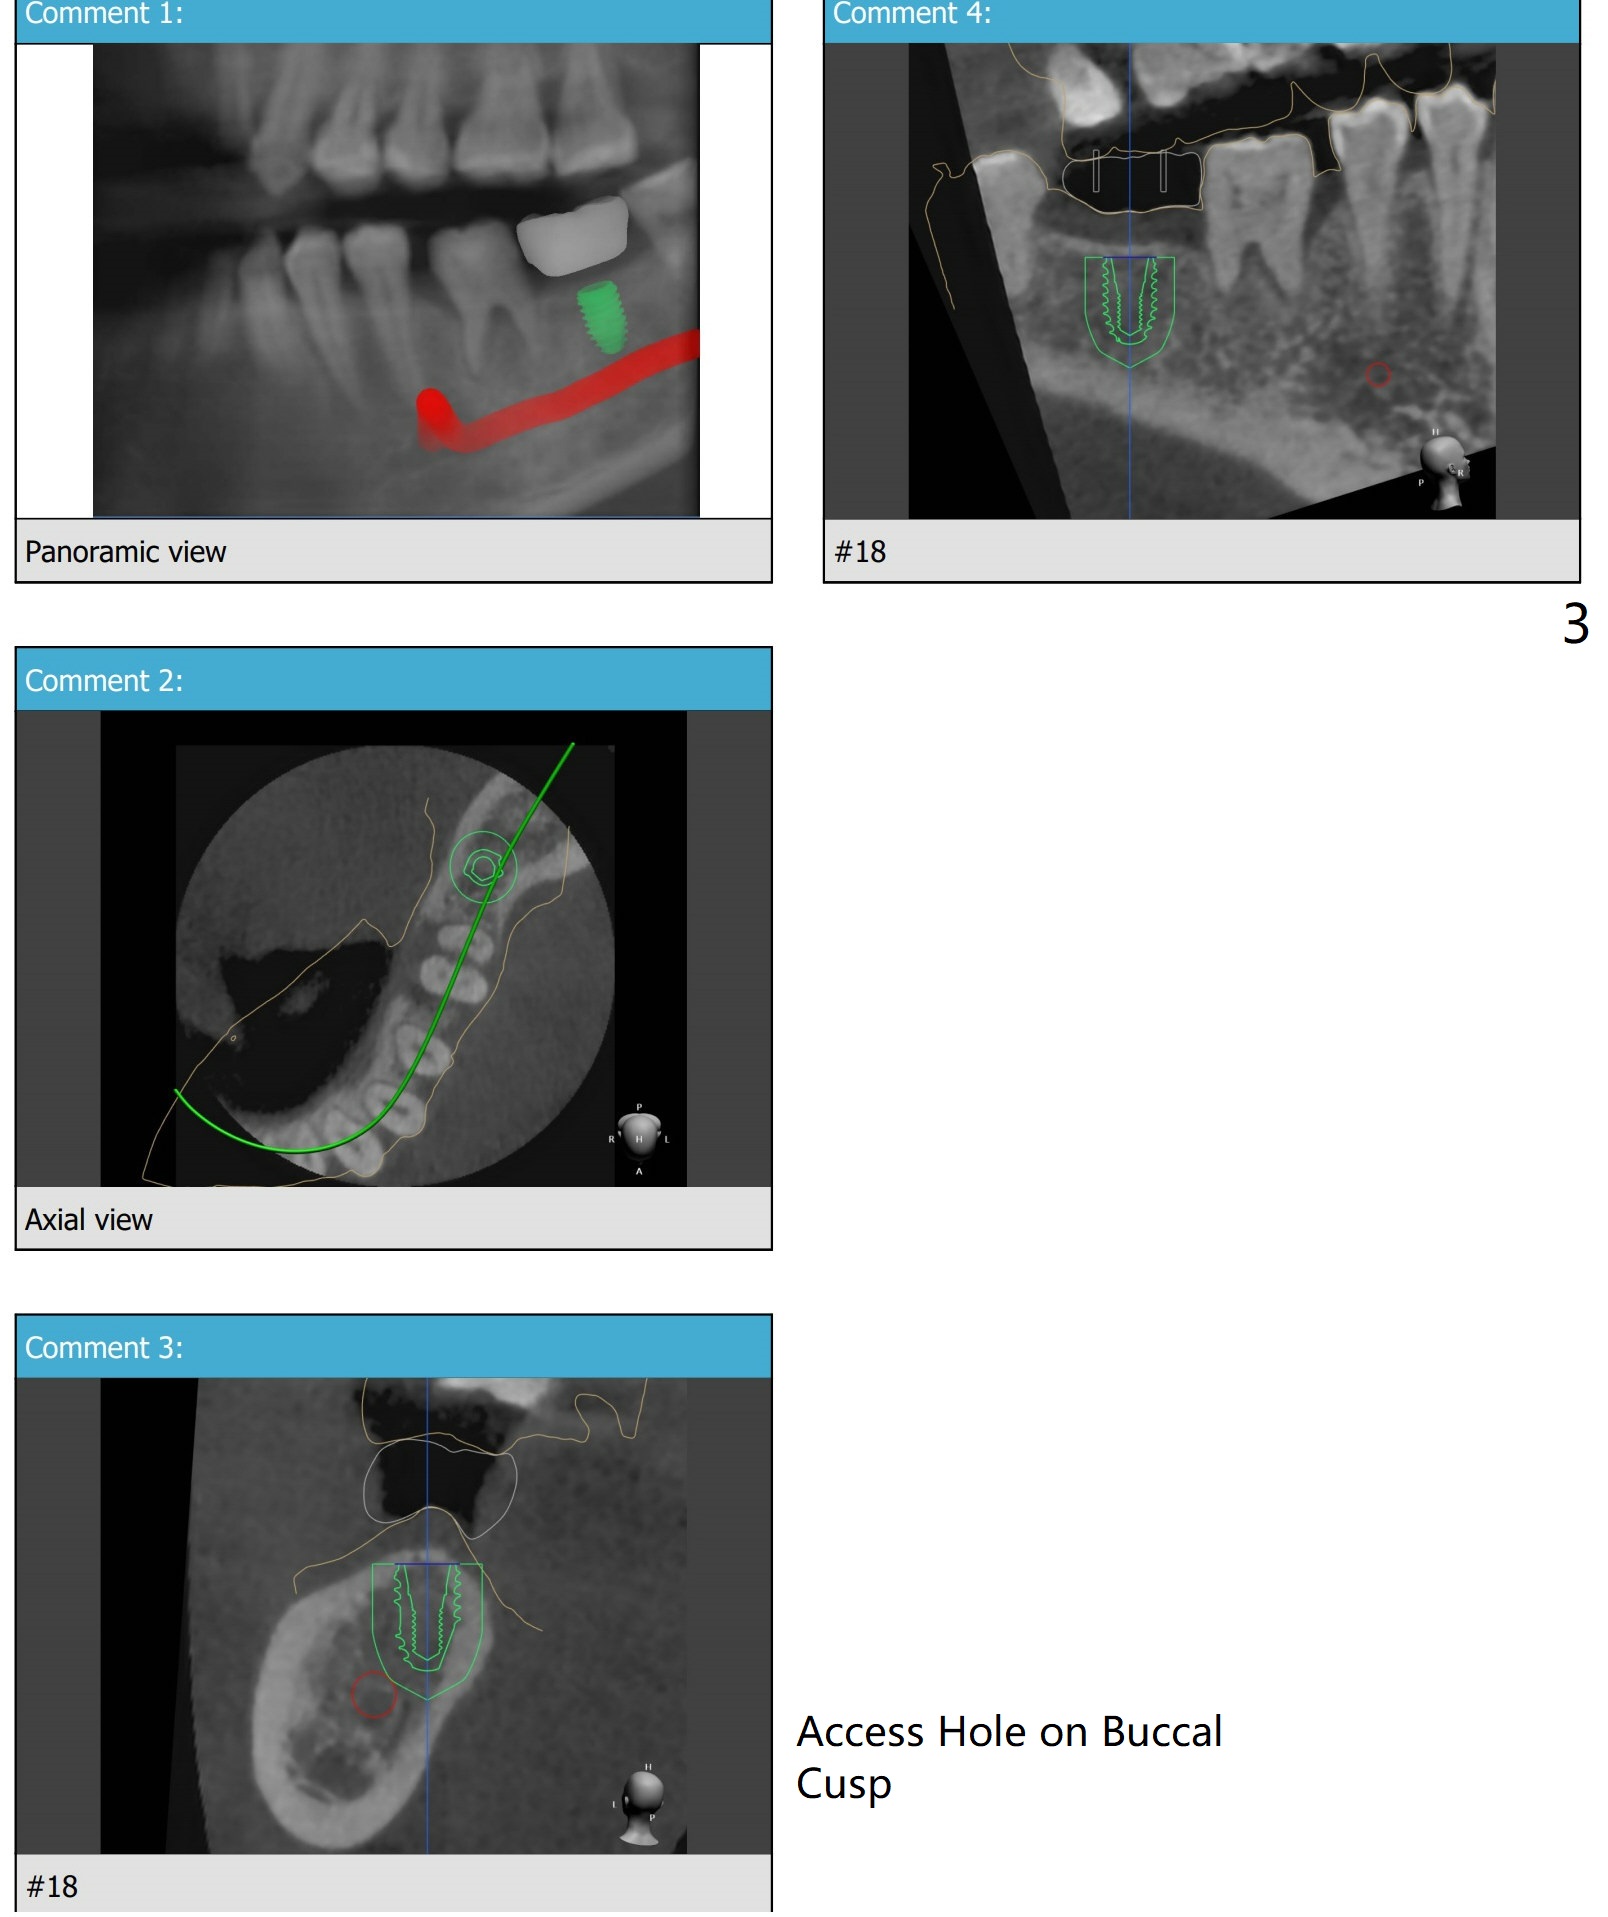

Narrow Ridge

A 35-year-old woman